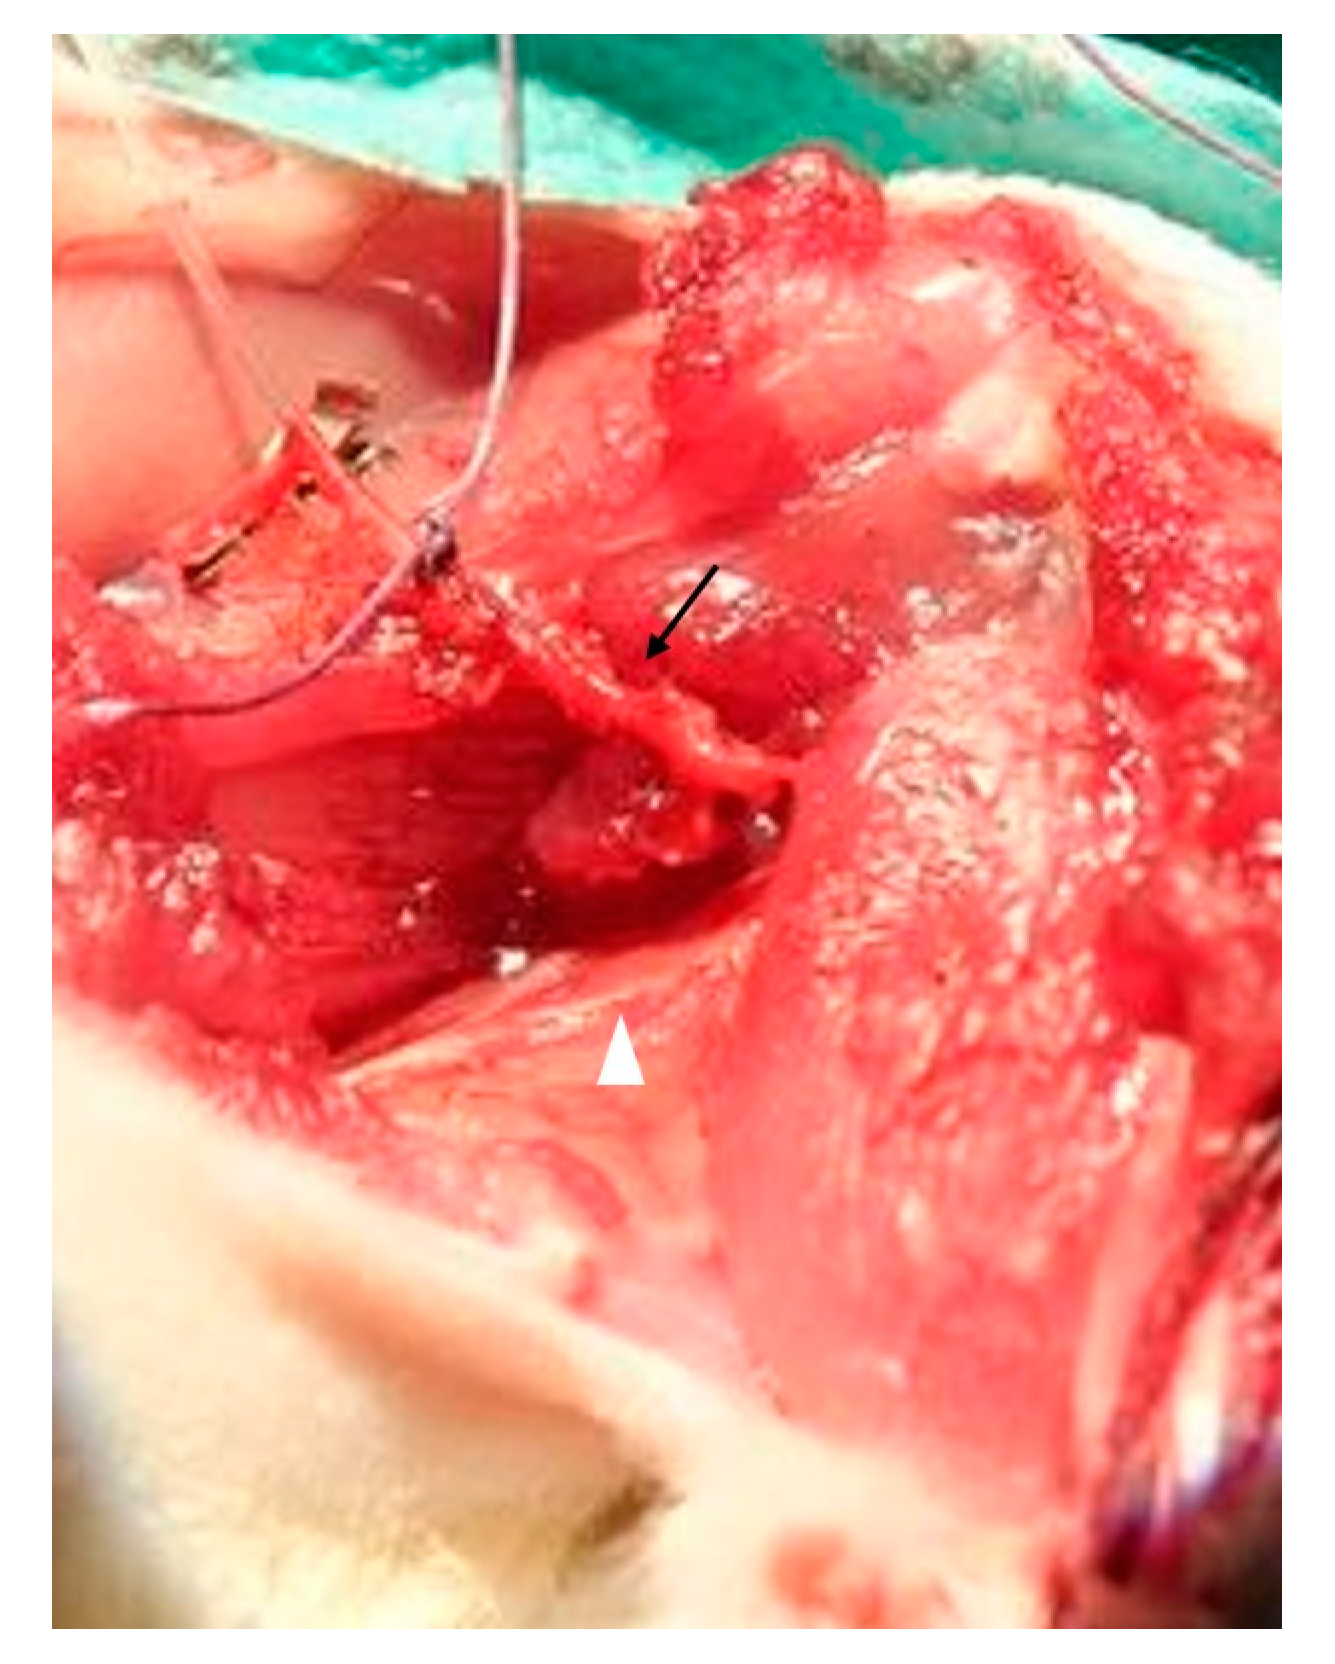

2.2. Muscle Preparation

2.4. Muscle Transplantation

3.1. Surgery and Animals